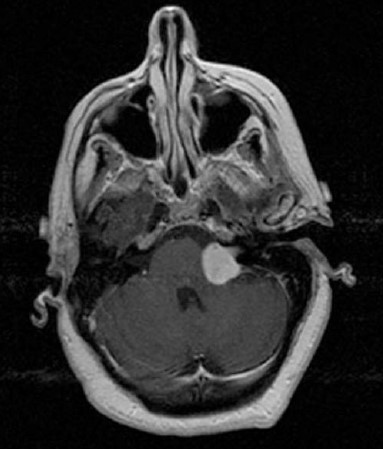

As seguintes afirmações são verdadeiras sobre o diagnóstico mais provável representado na figura abaixo, EXCETO:

Provas